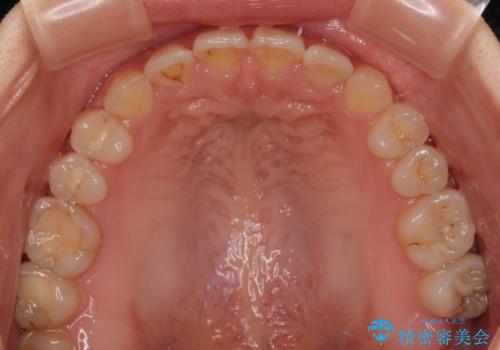

- 前歯の開咬を気にして来院された患者様です。

開咬の治療は、前歯を閉じるように動かすとともに、上下臼歯を圧下(骨内にめり込ませる)させることで進めて行きます。

インビザラインは臼歯の圧下を効果的に行えるため、インビザラインを用いて矯正治療を行うこととしました。